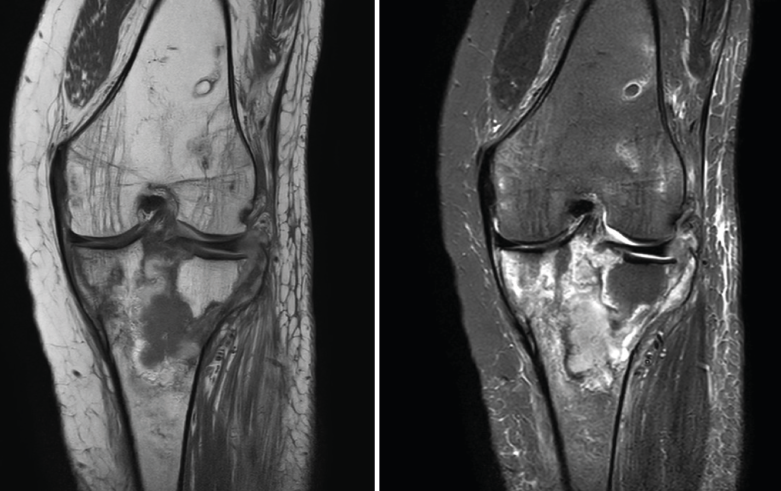

Los infartos medulares óseos aparecen en el 0,06% de los pacientes a quienes se les ha realizado una RM del aparato locomotor. Se presentan como lesiones segmentarias, puramente medulares, sin afección cortical, normalmente múltiples y que afectan predominantemente a los huesos largos de las extremidades, sobre todo las inferiores. La RM es esencial en el diagnóstico por imagen, apareciendo como lesiones óseas intramedulares de contornos serpiginosos hipo- o isointensos en secuencias T1 e hiperintensos en T2. Por tanto, la RM es el instrumento crucial en las fases iniciales, ya que permite caracterizar las lesiones y proceder a su diagnóstico temprano(19)(Figura 52).

Figura 52. A: corte de secuencia coronal T2 Fat-Sat con infartos óseos en el fémur y la tibia; B: corte de secuencia sagital T1 con infartos óseos en el fémur y la tibia.